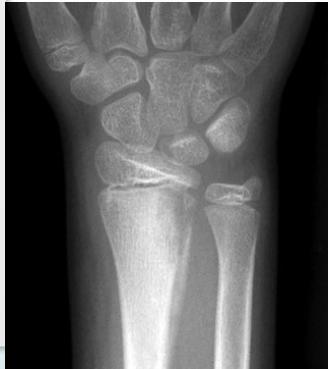

X-rays

- Which bone, and which site in bone?

- Solitary or multiple?

- Bone forming or bone eating?

- Margins: well-defined or ill-defined?

- Calcifications in the lesion?

- Is cortex eroded or destroyed?

- Is there periosteal new bone formation?

- Soft tissue extension?